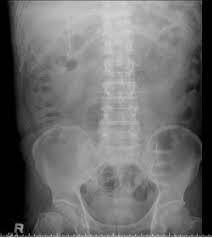

Plain X Ray Of Abdomen Shows The Tip Of The Vp Shunt Was Curling Over Download Scientific Diagram